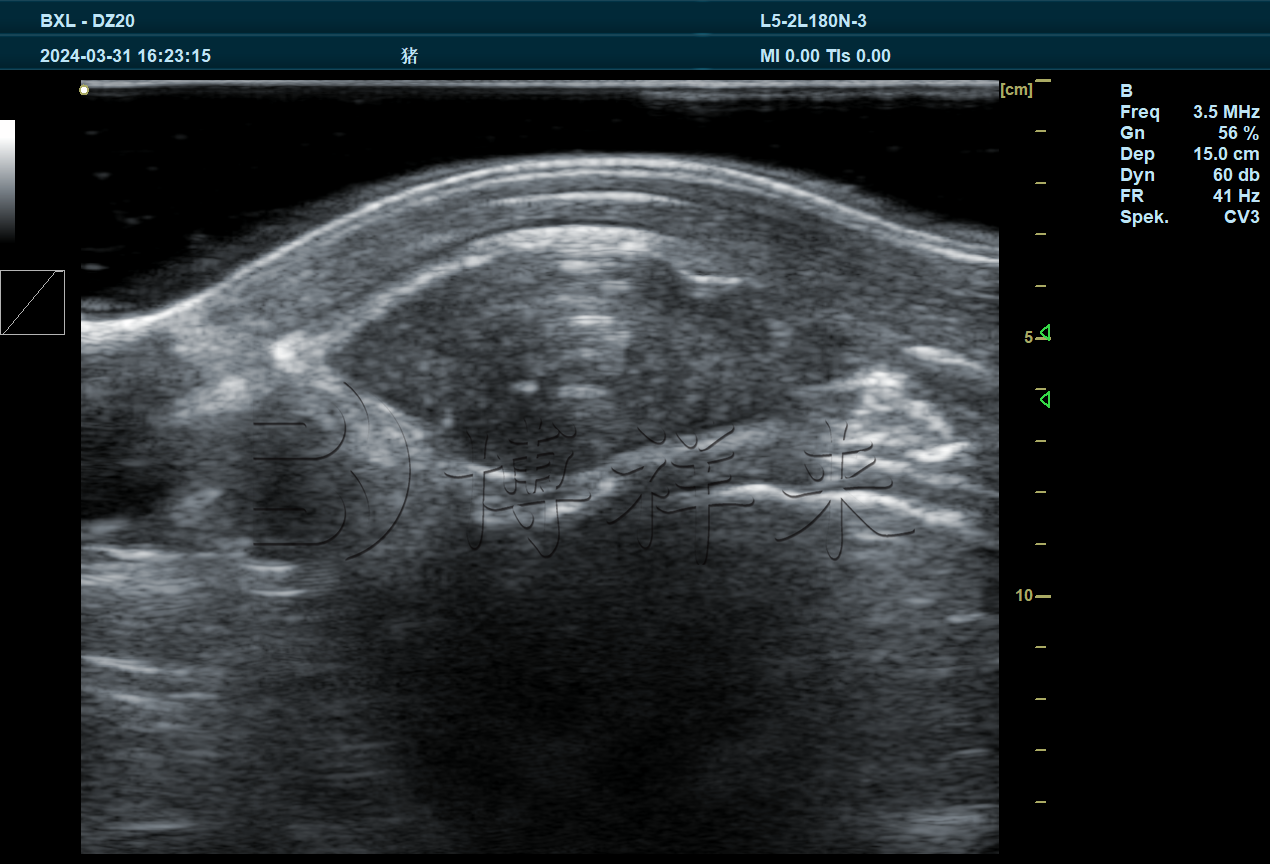

BXL-DZ20是一款多功能兽用全数字彩色多普勒B超仪,可以适配多种探头进行不同超声检测,包括猪牛羊妊娠检测,胎儿发育情况,卵泡黄体发育情况,死活胎,多胎检测,马肌腱韧带检测,背膘眼肌检测等。

4.1、BXL3.5L15A,16cm背膘眼肌专用探头

实拍图片

图像特点